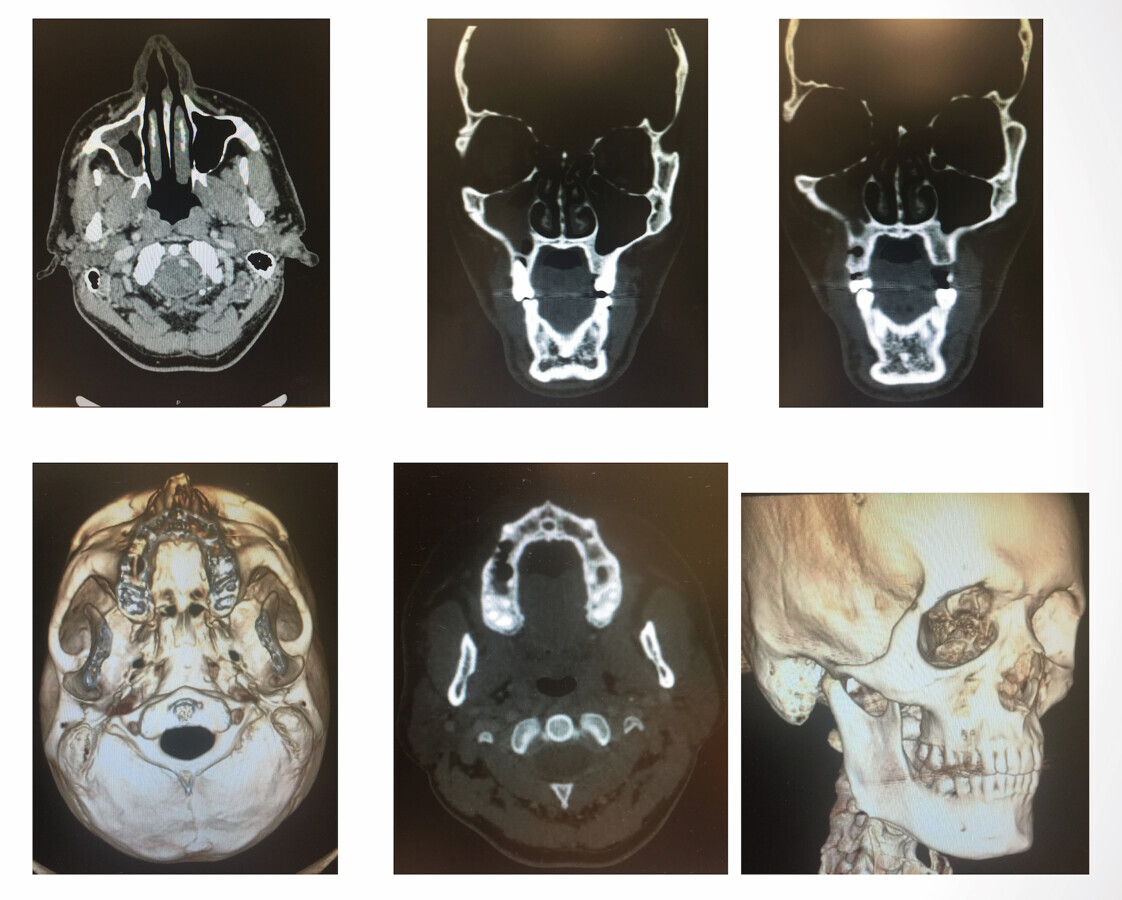

Guía Clínica para la atención odontológica del paciente con cáncer oral (4)

Detalle de la parte inferior de la boca de una paciente afectada por mucositis oral como consecuencia de cáncer oral. Foto: SECIB